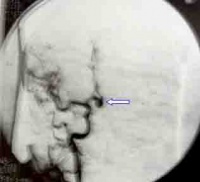

对患者进行TCD监控和头颅CT复查,发现有脑血管痉挛或脑积水及时处理,怀疑动脉瘤或血管畸形,通过DSA确诊,神经外科进行处理。脑血管造影是确诊动脉瘤的金标准,一般选在发病后三天内或三周后。